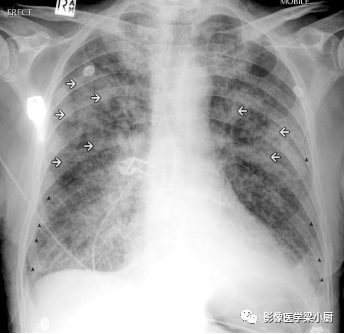

急性肺水肿患者X线图像:双肺外野可见Kelery B 线(黑色箭头),为间质性水肿表现。双肺同样可见趋向于融合的结节性阴影(白色箭头),为肺泡性肺水肿表现。